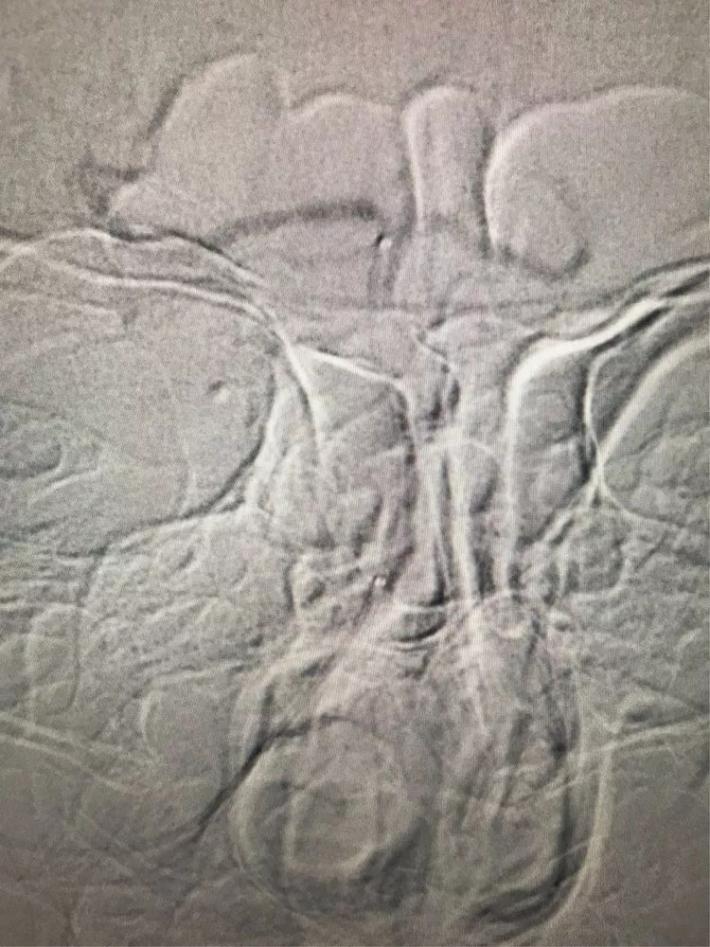

MRA检查显示:基底动脉闭塞。

手术步骤

桥接动脉取栓,造影显示:基底动脉闭塞。

微导管进入基底动脉尖部,显示进入真腔。

置入支架,见基底动脉有血流。

取出支架,血管闭塞。

第二次上微导管进入真腔。

置入支架,基底动脉有血流。

取出支架,血管未开通。

第三次上微导管。

支架打开取栓。

见基底动脉血流恢复,左侧大脑后动脉血流欠佳。